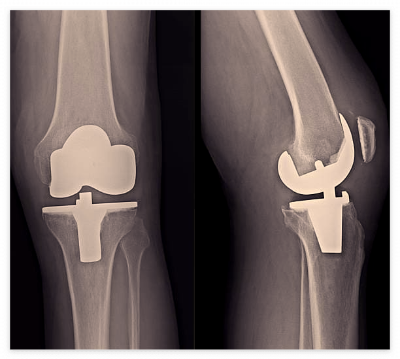

1. 무릎 인공관절 수술이란?

퇴행성 관절염, 류마티스 관절염 등으로 무릎 연골이 닳아 통증과 운동 제한이 심할 때 시행하는 수술입니다.

손상된 관절을 금속, 세라믹 등 인공관절로 대체하여 기능을 회복하는 치료법입니다.

Q. 로봇 인공관절 수술도 보험 적용되나요?

→ 로봇수술은 대부분 비급여 항목입니다. 다만 표준 인공관절 수술비는 보험 적용됩니다.